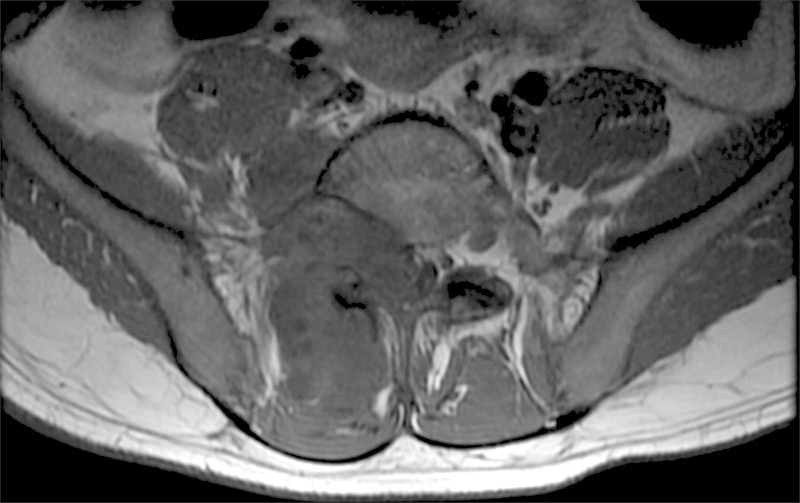

研究设计案例报告。目的:本研究的目的是报道腰椎骨痛风的发生。方法通过一个病例报告来说明脊柱痛风的要点,我们简要回顾了痛风的文献,因为它与骨科和脊柱表现以及管理指南有关。结果:本病例报告详细描述了一名24岁男性腰椎痛风病史和3年进行性背痛的重大临床发现。结论高怀疑指数有助于腰痛或有痛风病史的神经系统疾病的诊断。既往痛风史(尤其是痛风石)、高尿酸血症和影像学特征有助于临床医生诊断脊柱性痛风。早期诊断有可能避免手术干预的需要。

Study Design Case report. Objective The objective of this study is to report the occurrence of tophaceous gout in the lumbar spine. Methods Using a case report to illustrate the key points of gout in the spine, we provide a brief review of gout in the literature as it relates to its orthopedic and spinal manifestations as well as guidelines for management. Results This case report details the occurrence of a large and clinically significant finding of tophaceous gout in the lumbar spine in a 24-year-old man with a known history of gout and a 3-year history of progressive back pain. Conclusion A high index of suspicion can assist in diagnosis of patients presenting with back pain or neurologic findings with a history of gout. A previous history of gout (especially the presence of tophi), hyperuricemia, and the radiological characteristics presented here should aid the clinician in making the diagnosis of spinal gout. Early diagnosis has the potential to prevent the need for surgical intervention.